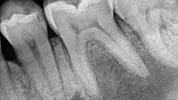

Radiographic exam

Take quality radiographs that are angulated correctly. Often two or more angles are necessary. Look for evidence of faulty restorations, caries, or changes in the PDL or periradicular radiolucent areas. This is also an opportunity to begin to appreciate the anatomy and potential complications that may arise in treatment. After radiographs are obtained, the answers to the previous questions can begin to be correlated with radiographic findings. A common error is to make a diagnosis before completing all phases of the exam.